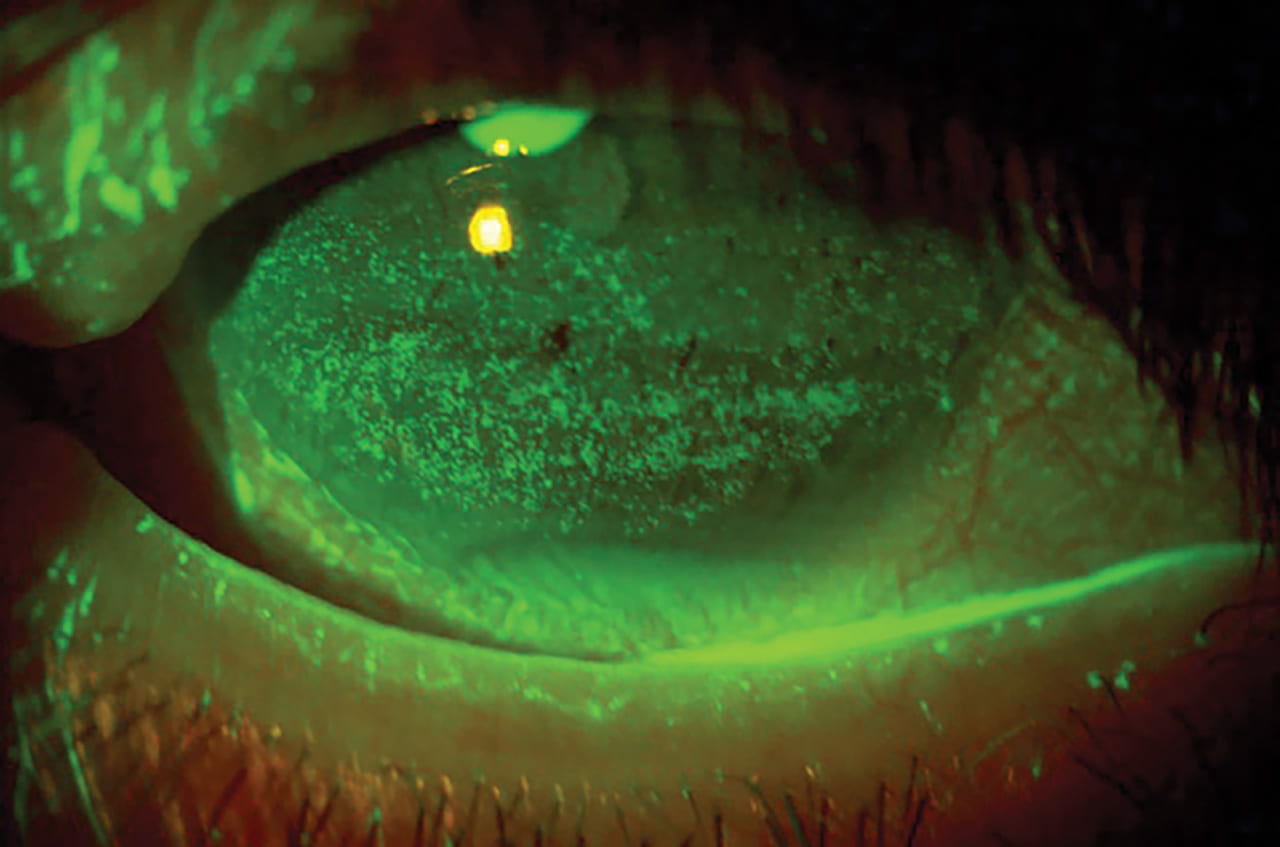

Given the deleterious effects of dry eye disease (DED) on the tear film, cornea, and conjunctiva, its prevalence among our patients, and its negative effect on refractive surgery outcomes, reviewing current at-home treatments makes sense.